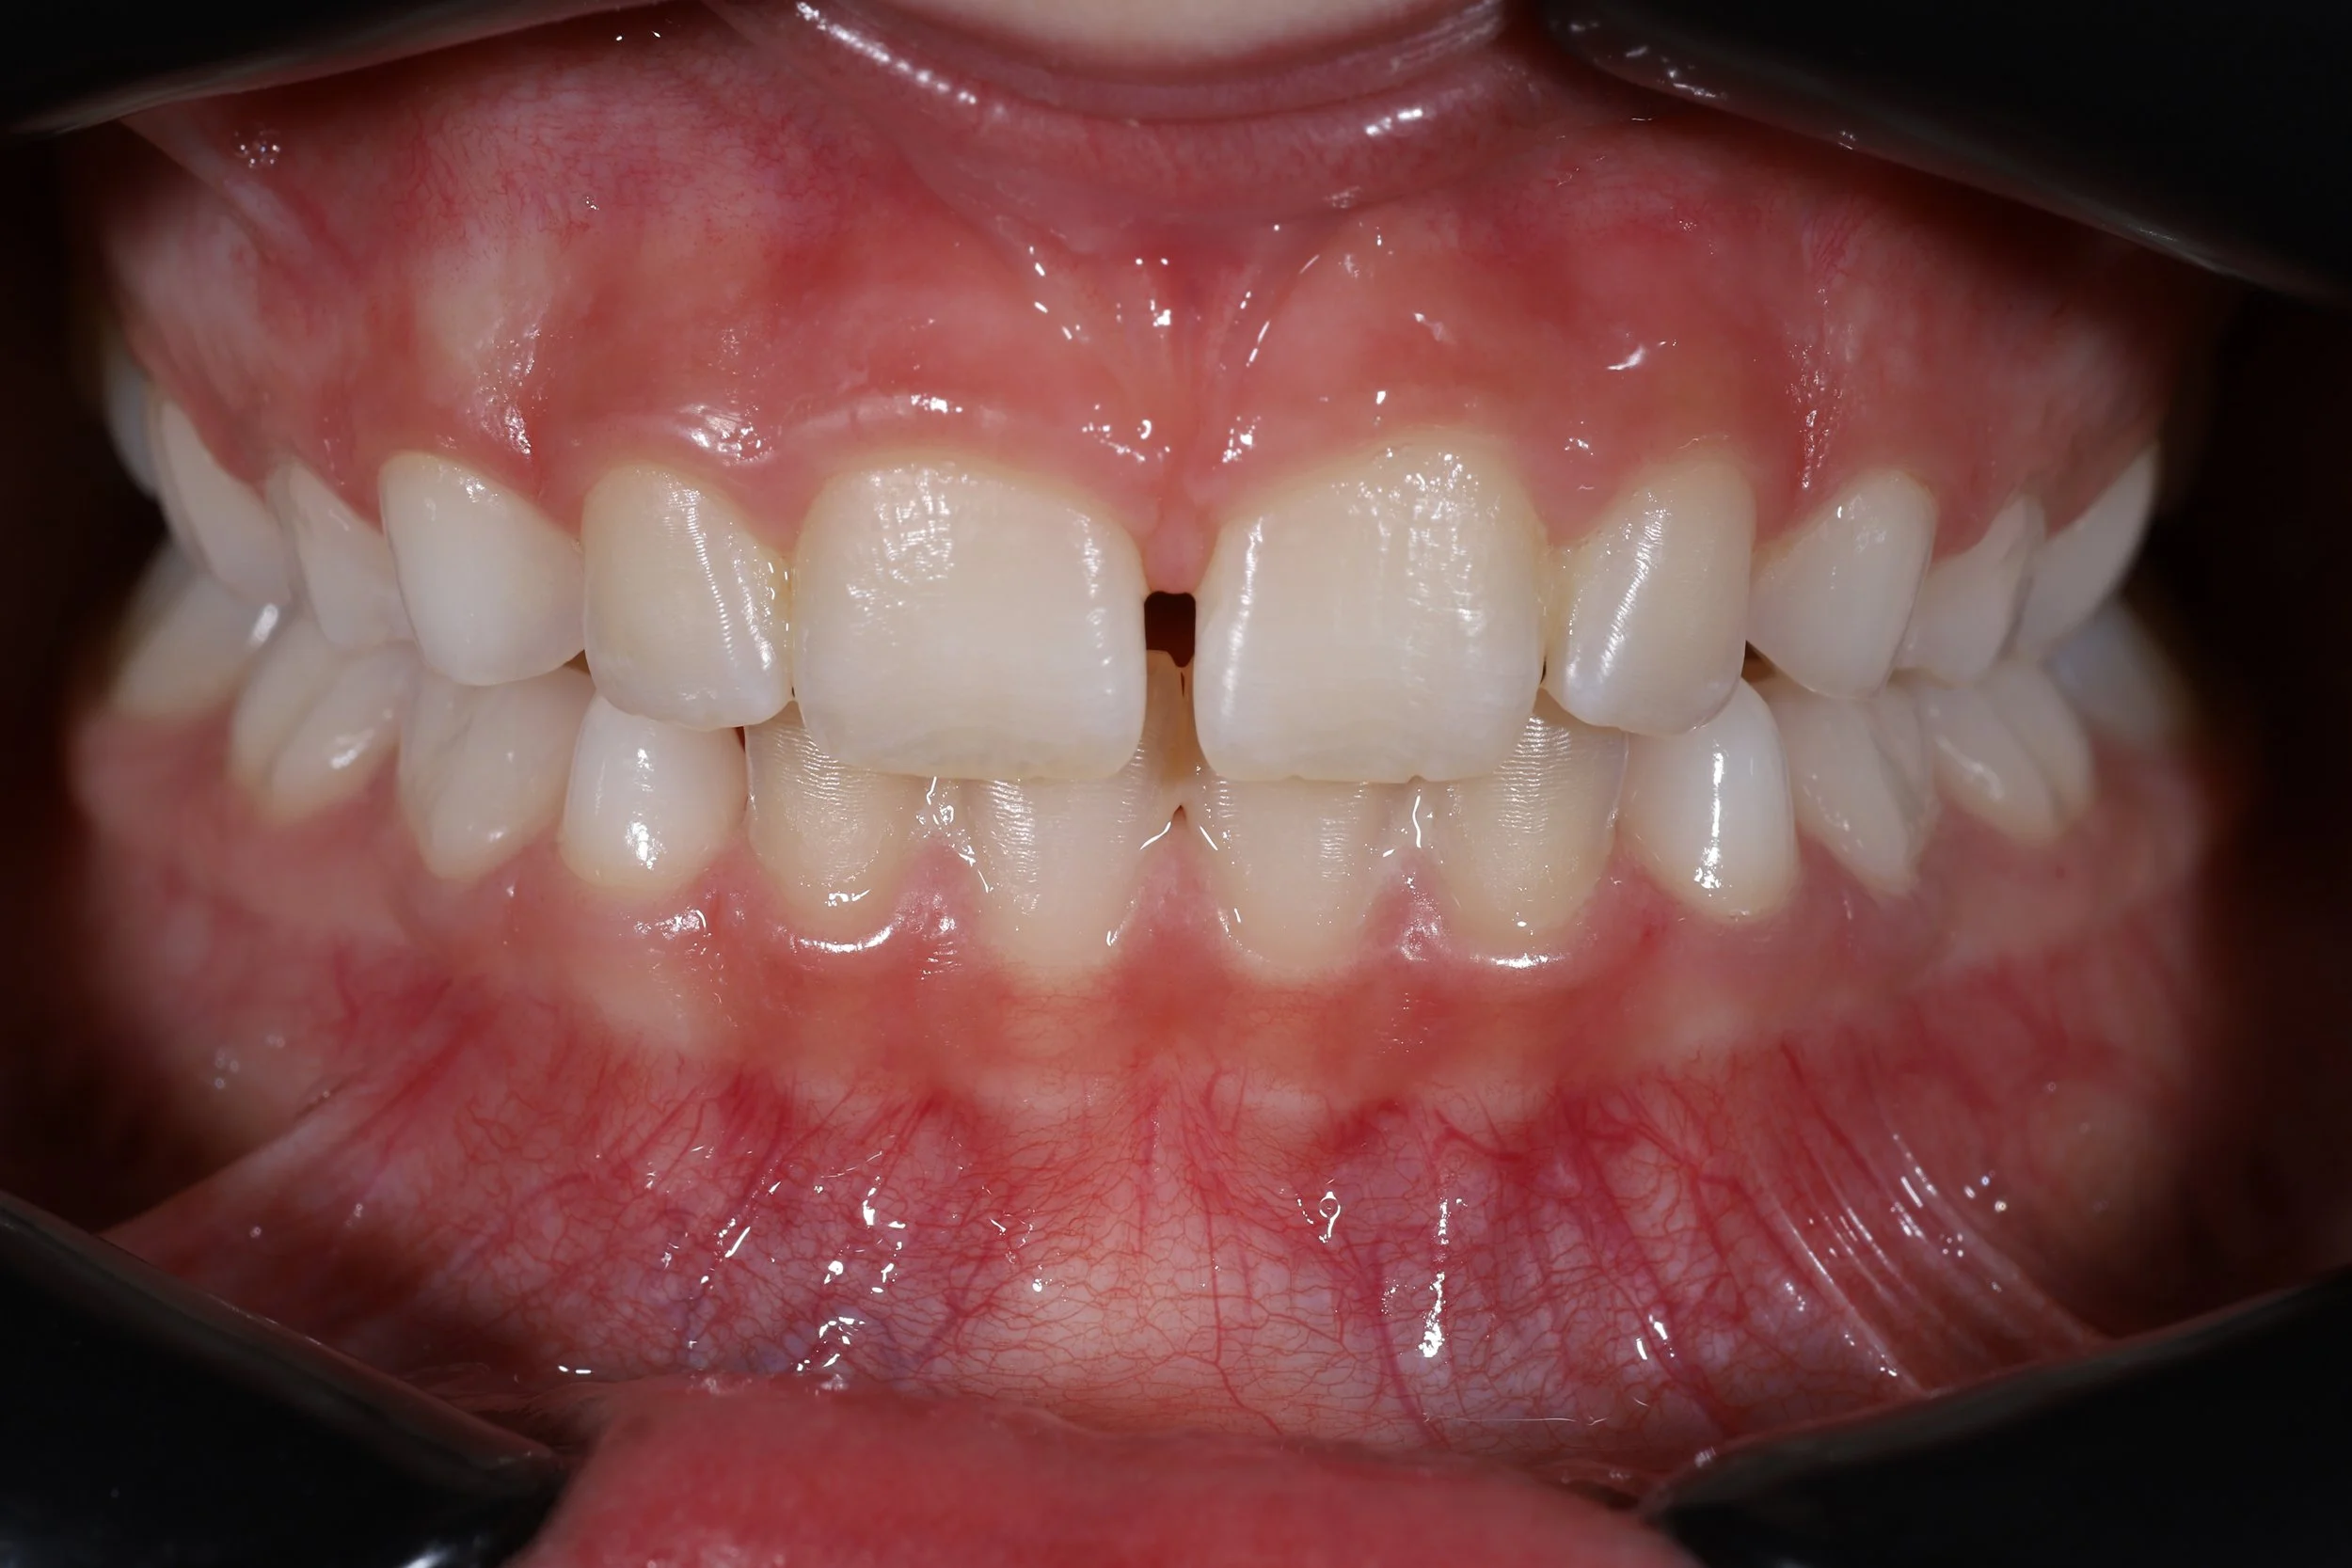

My journey in dentistry started at a young age. I only had 8 of my 20 baby teeth and was missing 15 of my front 20 teeth.

This meant referral to Newcastle Dental School at the age of 5, Dentures all of my childhood with the intention of implant placement when I’d stopped growing.

At 18 I had applied to study at The Charles Clifford Dental School in Sheffield, My care was then transferred to Raj Patel (still a good friend today)